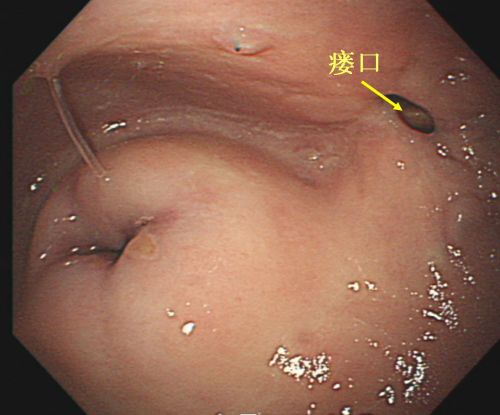

阴道镜提示瘘口位于宫颈旁。